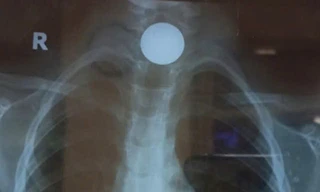

Từ khóa: "cấp cứu hóc dị vật"

1 kết quả